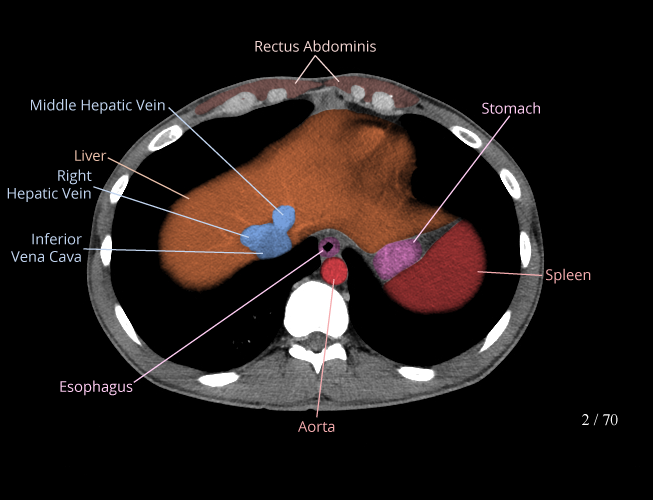

Body

Covers abdominal CT anatomy.